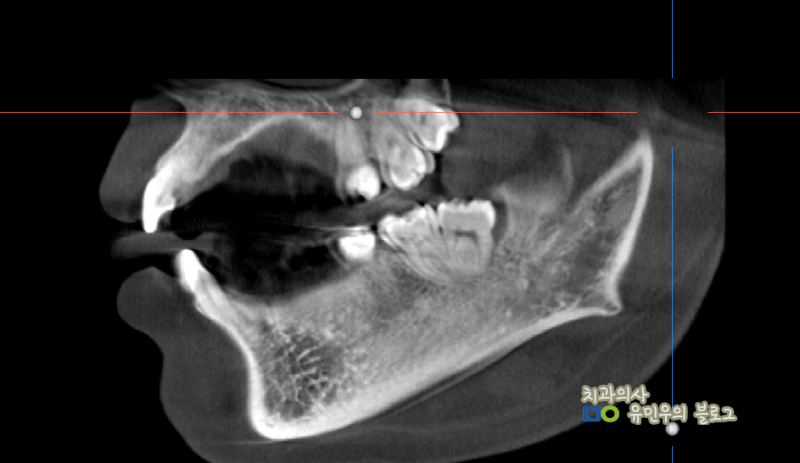

양쪽 아래 사랑니를 보면 맹출 방향이 역방향임을 알 수 있다. 사랑니를 앓는 환자들이 나중에 치과에 와서 사진을 보고 설명을 하면 치아가 수평이 아닌 것을 다행이라고 생각하는 경우가 많다. 그러나 치아가 뒤를 향하고 있을 때는 뒤쪽의 턱뼈가 치아를 매우 강하게 지지하고, 앞쪽과 반대 방향, 즉 발치 방향이 되어 있어 장치 접근이 어렵다. 위의 경우 치아의 뿌리도 많이 휘어져 있고 치아가 매우 커서 치아를 발치하기 어려운 상황에 해당합니다. 이 부분은 환자에게 치아발치를 했다고 충분히 설명을 드렸는데요, 위의 예에서는 사진상으로 양쪽 아래 사랑니와 오른쪽 위(실제로는 왼쪽 위) 사랑니를 포함하여 2~3개의 사랑니를 발치하였습니다.

사진 왼쪽 하단에 있는 사랑니였는데 뿌리가 휘고 머리가 너무 커서 치아가 여러 조각으로 쪼개져 뽑혔습니다. 치근이 뼈에 단단히 부착되어 발치가 어려웠지만 치근을 포함한 모든 치아가 깨끗하게 발치되었습니다. 사랑니 발치의 난이도는 엑스레이로 대략적으로 예측할 수 있지만 실제로는 치아 뿌리의 유착 정도와 환자 뼈의 경도도 중요하기 때문에 발치에는 실제로 시간이 걸린다. 시기에는 약간의 차이가 있을 것입니다. 골드내추럴치과에서는 다양한 사랑니 발치 경험 사례를 통해 가장 빠르고 불편함이 적은 사랑니 발치를 위해 노력하고 있습니다. 공포감이 강해 사랑니 발치를 미루게 되면 나중에는 염증으로 인해 발치시 더 큰 불편함을 유발할 수 있으며 앞니에도 악영향을 미칠 수 있습니다. 이는 보통 사람들이 걱정하는 것과는 다르고, 평소에 쉽게 할 수 있는 일이니 두려워하지 마시고, 다른 치아에 염증이 생기거나 다른 치아 건강 문제로 진행되기 전에 적절한 상담과 치료를 통해 치아 건강 문제를 보호하시기 바랍니다. .나는 희망